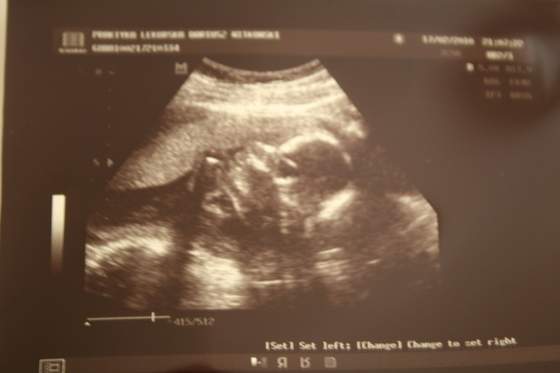

badanie usg tuż przed porodem jest niepotrzebne bo przy tak dużym dziecku położna wie jak jest ono ułożone -jeśli maluchowi coś się poplącze i inaczej zegnie główkę są sposoby ułożenia ciała które pomogą malcowi wrócić "na właściwe tory"